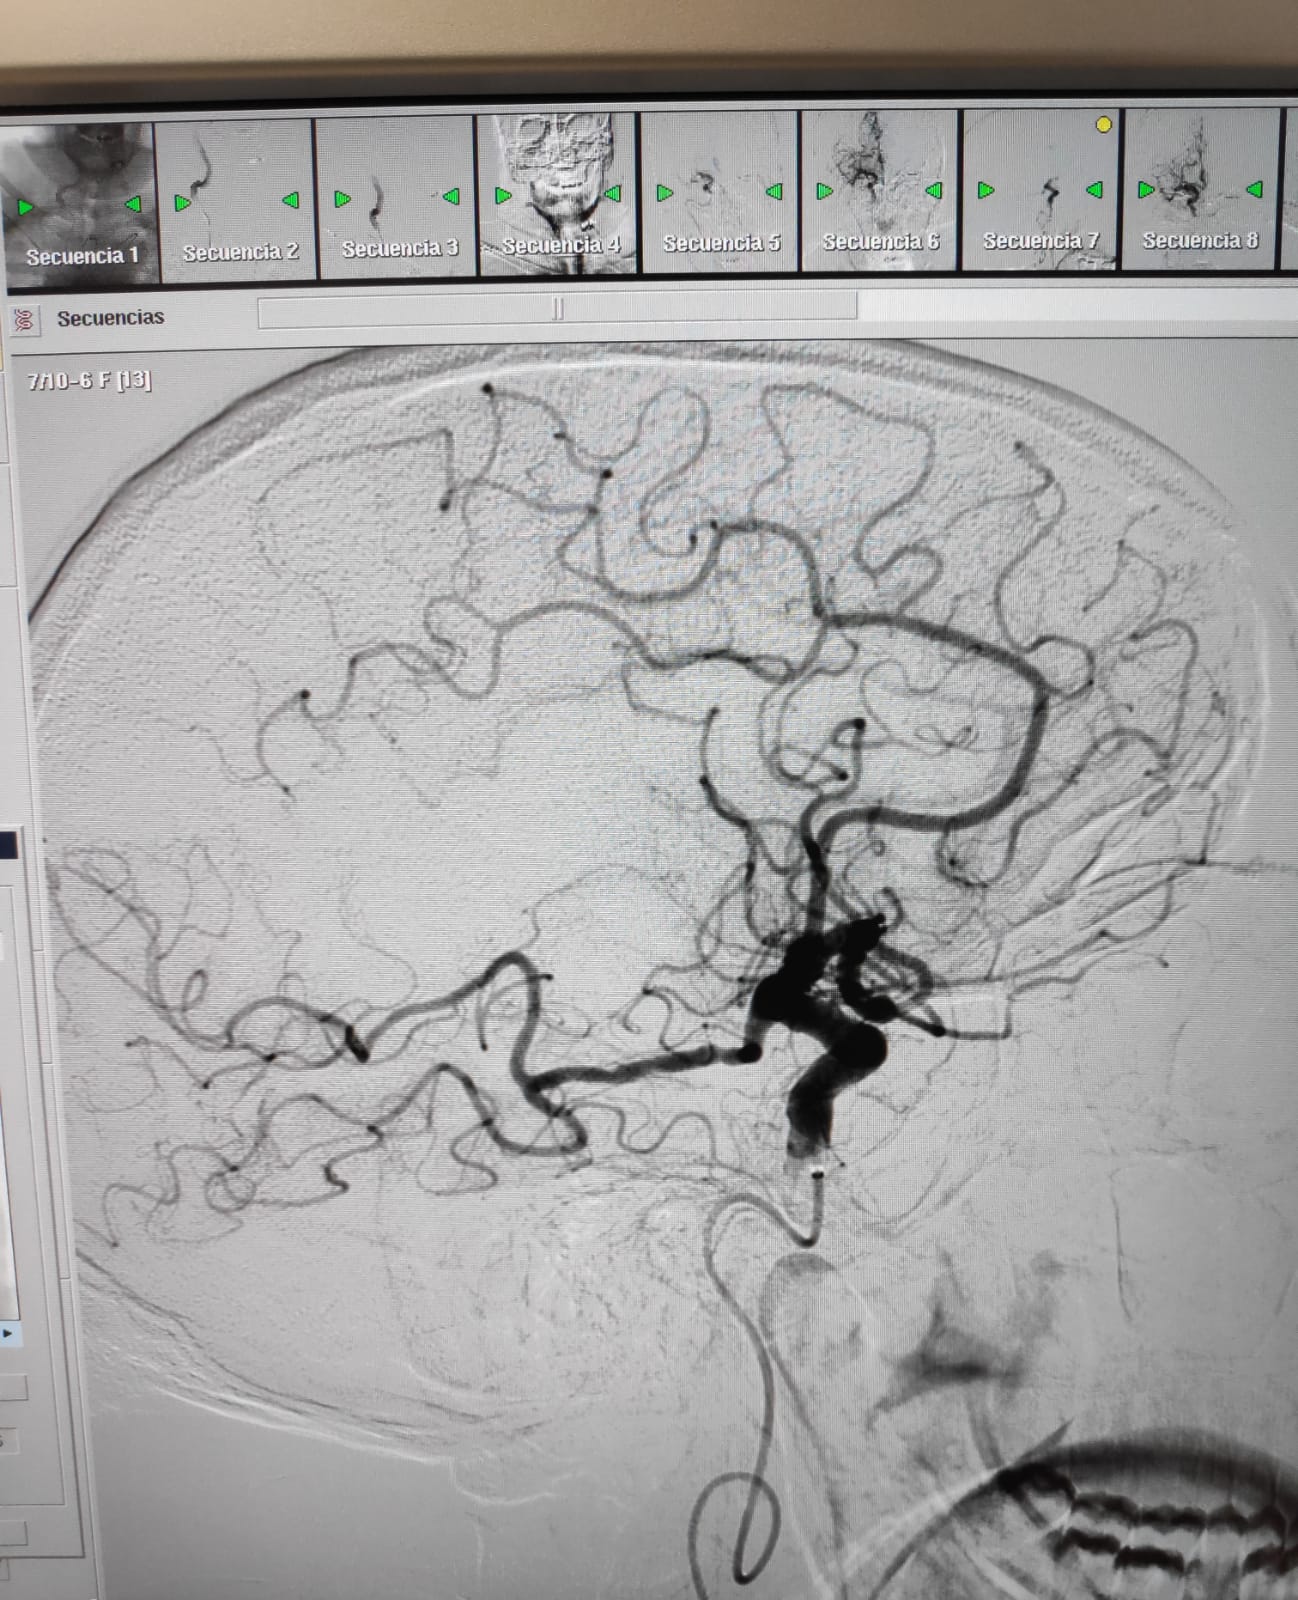

La sala de radiologia intervencionista durant la realització d'una trombectomia mecànica a un pacient que havia patit un ictus isquèmic.

En aquestes dues imatges, podem veure com queda afectada la circulació arterial arran d'un ictis isquèmic i com es recupera després del tractament endovascular.